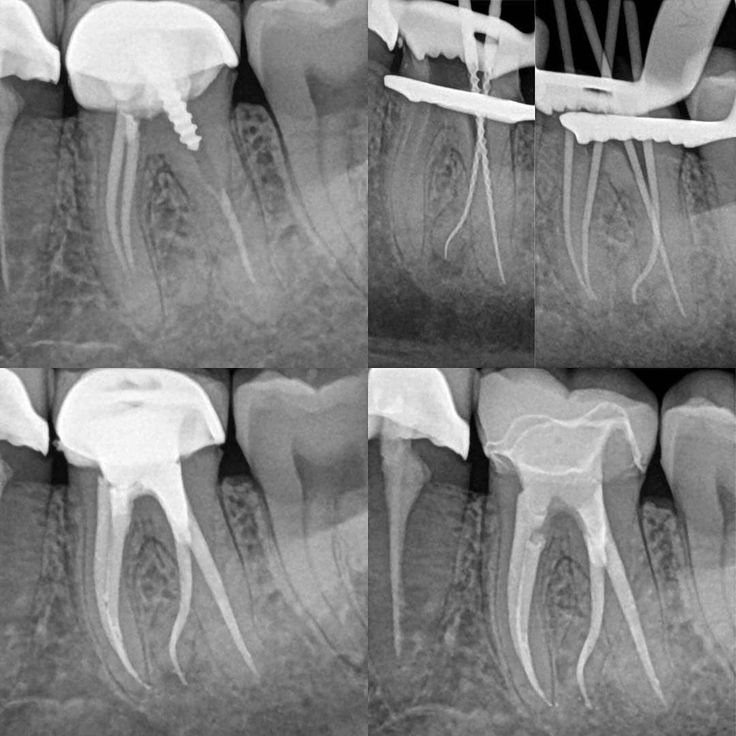

β€’Root Canal Therapy: Cleaning and sealing the tooth to eliminate infection.